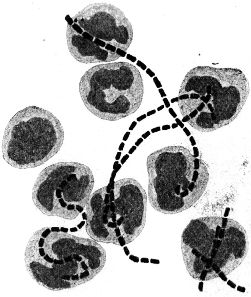

Abb. 2

Abb. 2.

Ausstrichpräparat von menschlichem Zahnschleim, gefärbt, etwa 1000fach vergrößert. Mannigfaltige Bakterien in buntem Gemisch.